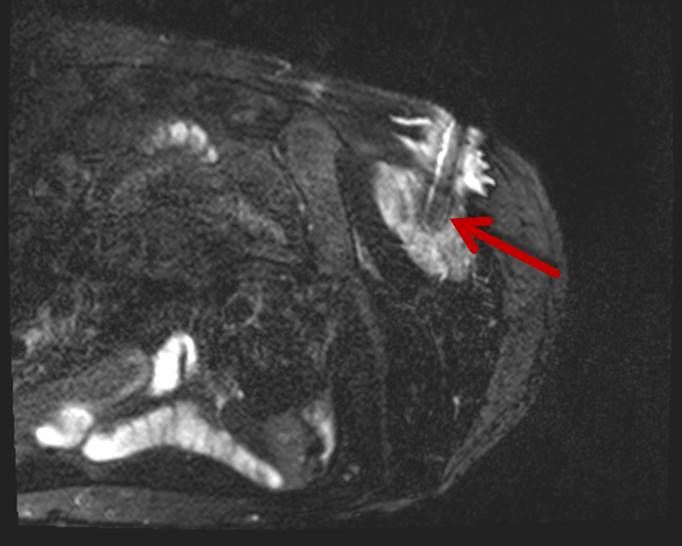

Eine Vielzahl von Krankheitsdiagnosen basiert auf der mikroskopischen bzw. histologischen Untersuchung körpereigener Gewebe, die auf möglichst schonende Weise entnommen und anschließend im Labor bzw. unter dem Mikroskop untersucht werden. Bei der perkutanen Biopsie punktiert der Arzt mit einer dünnen Nadel durch die Haut hindurch ('perkutan') das Zielorgan und entnimmt so eine kleine Menge Flüssigkeit oder ein kleines Gewebestück. Der Eingriff kann im Regelfall in örtlicher Betäubung durchgeführt werden. Um das Zielgewebe möglichst sicher zu treffen, führen wir die meisten Biopsien unter CT-Steuerung, alternativ unter sonographischer Steuerung, durch. Ist die Zielläsion nicht sicher im CT oder im Ultraschall zu erkennen, führen wir die Biopsie mit speziellen Biopsie-Systemen im Einzelfall auch unter MRT-Kontrolle durch.